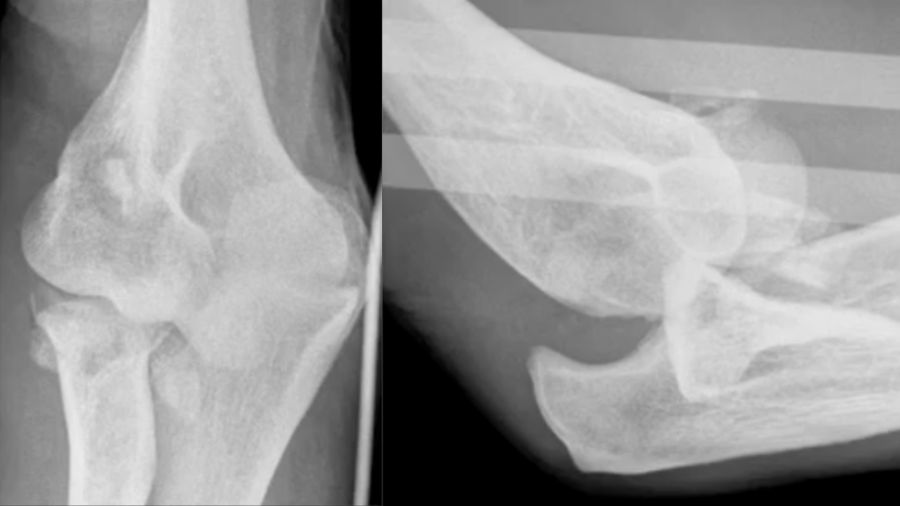

The coronoid fracture: classifying the damage

Shaun O’Driscoll’s coronoid classification system assesses the severity of coronoid fractures. The location and size of the fracture play a critical role in determining the treatment plan. For instance, a radial-sided tip fracture may not have as much impact on stability as a fracture involving the anteromedial facet.

The images demonstrate various coronoid fracture patterns, from minor tip fractures to complex fractures that involve multiple areas of the coronoid. Understanding the exact nature of these fractures—often via CT scans—is essential for effective treatment planning.